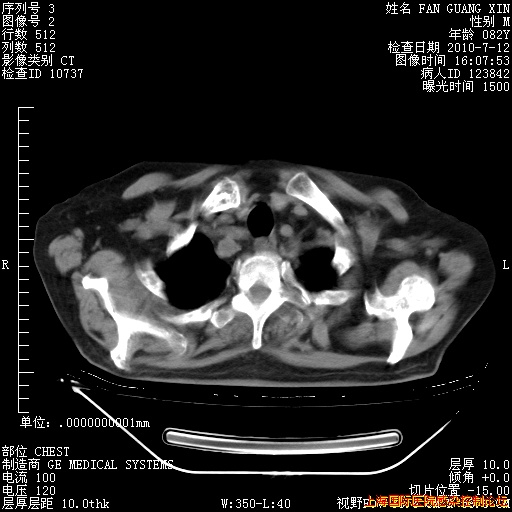

6月12日纵膈窗

今天复查CT

今天CT

整整相隔30天的肺部CT好像有所好转啊。甲强龙减量第3天,需要观察体温。

海管,自昨日你和我通完话后,不知您岳父消化道症状有无缓解?体温怎样?阅读7.12日胸部ct,个人认为目前激素治疗是有效的,甲强龙减量是适宜的。因在抗痨治疗,需密切观察肝功、肾功能和血常规。不过,老年、长期住院和大量使用激素,很担心菌群失调发生